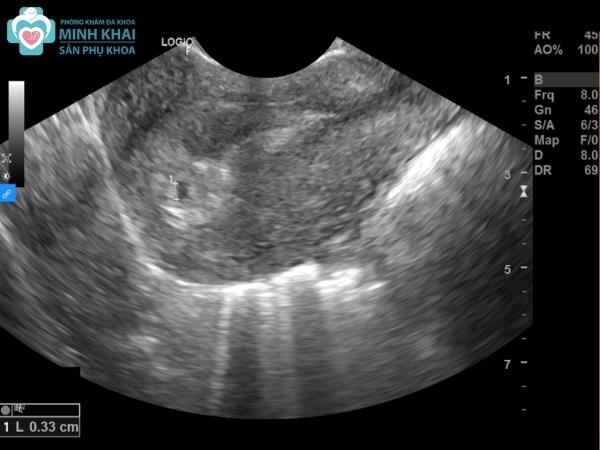

Trong giai đoạn đầu, siêu âm 2D có thể cho biết chính xác liệu người phụ nữ có mang thai không. Ngay ở tuần thứ 1-2 của thai kỳ, hình ảnh siêu âm thai 2D đã thể hiện được rõ ràng hình ảnh phôi thai có ở tử cung mẹ bầu. Tuy nhiên ở một số trường hợp bào thai di chuyển chậm thì hình ảnh siêu âm em bé sẽ rõ ràng hơn ở tuần thứ 3.

Kiểm tra mang thai ngoài tử cung

Một ưu điểm của siêu âm thai 2D là giúp xác định được vị trí của thai và biết nó có nằm bên ngoài tử cung hay đã đậu vào buồng tử cung của mẹ chưa. Nếu đã đi vào được tử cung thì phôi thai sẽ được đánh giá là an toàn. Còn không, mang thai ngoài tử cung sẽ rất nguy hiểm. Điều này cần phải được phát hiện sớm cũng như có những biện pháp can thiệp, đình chỉ thai kịp thời vì nó có thể gây nguy hiểm đến tính mạng của mẹ.